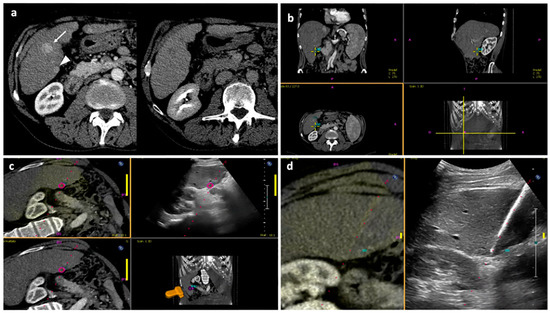

Figure 3. “Double fusion” technique—Part 1. (a) Pre-procedural axial CT images in the arterial and delayed phase showing a larger nodule with wash-in and wash-out consistent with HCC in segment V (white arrow), which was visible at US examination, and a smaller posterior subcapsular nodule with the same features (white arrowhead), which was not visible at US. The patient was scheduled for percutaneous MWA of the larger nodule under US guidance and of the smaller nodule with US fusion imaging guidance. (b) The smaller tumor is selected on the US scanner by visualization of pre-procedural CT images in the axial, coronal and sagittal planes. (c) Once registration of pre-procedural CT images to real-time US images are performed, the fused images are shown at the same time on the left upper quadrant of the US screen, simple US images are displayed on the right upper quadrant, CT images are shown on the left lower quadrant and the US probe 3D position is shown on the right lower quadrant. In this image, the smaller target tumor is visualized as a pink circle. (d) When US fusion imaging quality is judged adequate, the MWA antenna is placed into the target tumor; fused images are shown on the left while simple US images are shown on the right. Abbreviations—CBCT: cone-beam computed tomography; CT: computed tomography; MWA: microwave ablation; US: ultrasound.